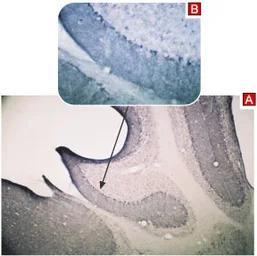

IHC-P analysis of mouse cerebellum tissue using GTX54860 TRPC3 antibody.

Panel A : Primary antibody

Panel B : Antibody preincubated with the control peptide antigen